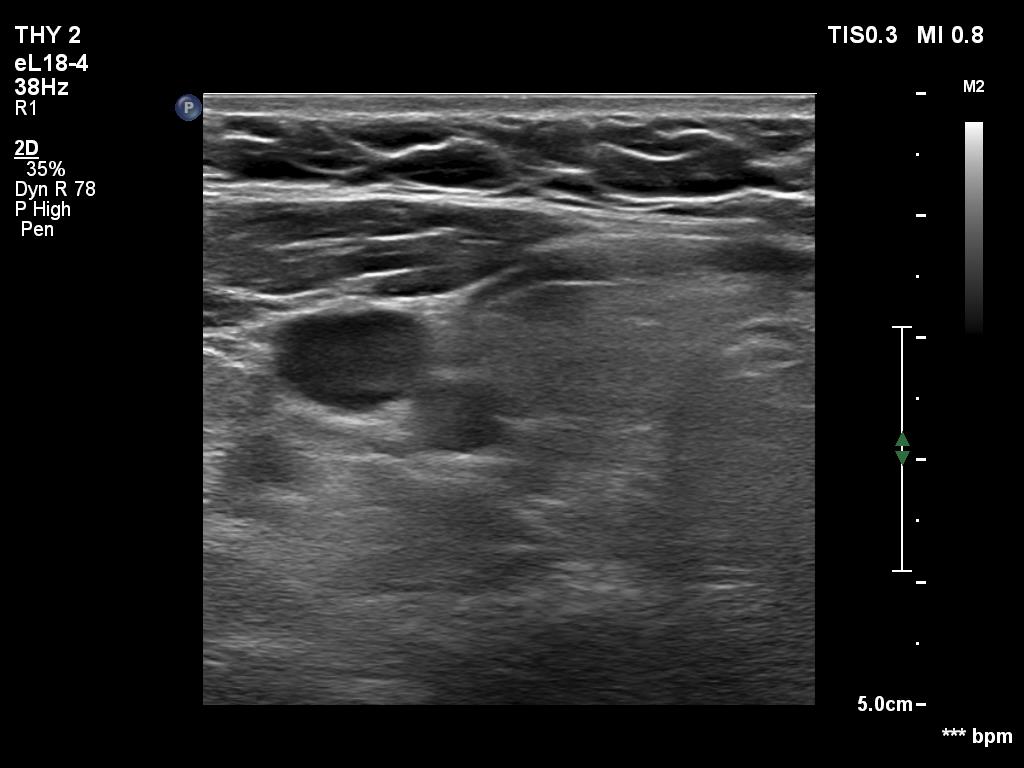

Ultrasonography. The thyroid was echonormal. Using higher frequency three discrete hypoechoic lesions were found, one in the middle dorsal part of the right lobe, one in the middle and a third one in the lower dorsal part of the left lobe. By decreasing the frequency, the presence of only the third one could be confirmed.

Comment. It is a rule that larger the distance from the probe worse the permeability of ultrasound wave. This can lead in certain patients (overweighted ones or frequently in men) that the dorsal part of the thyroid lobe can deceptively look darker, i.e. hypoechoic. If we have any doubt, by lowering the frequency i.e. increasing the penetrance, the real situation can be much better to judge.

This happened in this patient. If we would trust the pattern gained by higher frequency settings, we would falsely diagnose at least one additional nodule.